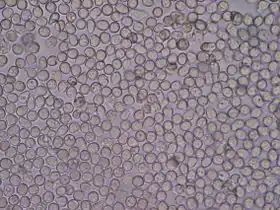

White blood cells seen under a microscope from a urine sample. | |

If microscopy is necessary, the urine is first centrifuged to concentrate the solid elements so that they can be viewed more easily. A drop of the concentrated sample is placed under a coverslip and examined, typically at 10x and 40x magnification.[5]:414–5 If it is necessary to determine the exact number of cells or casts in the sample, it can be placed in a counting chamber called a hemocytometer.[3]:461 Urine is traditionally examined by light microscopy, but some laboratories use phase-contrast microscopes, which improve the visualization of elements such as urinary casts and mucus.[5]:414–5 There are also automated systems that use flowresensce flow cytometry technology and others with pattern recognition to identify microscopic elements in the urine.[6]

Microscopic examination

The numbers and types of cells and/or material such as urinary casts can yield a great detail of information and may suggest a specific diagnosis.

- Hematuria – associated with kidney stones, infections, tumors and other conditions

- Pyuria – associated with urinary infections

- Eosinophiluria – associated with allergic interstitial nephritis, atheroembolic disease

- Red blood cell casts – associated with glomerulonephritis, vasculitis, or malignant hypertension

- White blood cell casts – associated with acute interstitial nephritis, exudative glomerulonephritis, or severe pyelonephritis

- (Heme) granular casts – associated with acute tubular necrosis

- Crystalluria – associated with acute urate nephropathy (or acute uric acid nephropathy, AUAN)

- Calcium oxalatin – associated with ethylene glycol, kidney stone disease

- Waxy casts – associated with chronic renal disease

Blood cells

| Red blood cells (RBCs) / erythrocytes |

0[13][18] | 2[13] – 3[18] | per High Power Field (HPF) |

May be present as intact RBCs, which indicate bleeding. Even a trace amount of blood is enough to give the entire urine sample a red/pink hue, with difficulty in judging the amount of bleeding from a gross examination. Hematuria may be due to a generalized bleeding diathesis or a urinary tract-specific problem (trauma, stone...urolithiasis, infection, malignancy, etc.) or artifact of catheterization in case the sample is taken from a collection bag, in which case a fresh urine sample should be sent for a repeat test.

If the RBCs are of renal or glomerular origin (due to glomerulonephritis), the RBCs incur mechanical damage during the glomerular passage, and then osmotic damage along the tubules, so dysmorphic features appear. The dysmorphic RBCs in urine most characteristic of glomerular origin are called "G1 cells", doughnut-shaped rings with protruding round blebs sometimes looking like Mickey Mouse's head (with ears). Painless hematuria of nonglomerular origin may be a sign of urinary tract malignancy, which may warrant a more thorough cytological investigation. |

| RBC casts | n/a | 0 / negative[13] | ||

| White blood cells (WBCs) / leukocytes / (pus cells) |

0[13] | 2[13] / negative[13] | ||

| – | 10 | per µl or mm3 |

"Significant pyuria" at greater than or equal to 10 leucocytes per microlitre (µl) or cubic millimeter (mm3) | |

| "Blood" / (actually hemoglobin) | n/a | 0 / negative[13] | dip-stick qualitative scale of 0 to 4+ | Hemoglobinuria is suggestive of in vivo hemolysis, but must be distinguished from hematuria. In case of hemoglobinuria, a urine dipstick shows presence of blood, but no RBCs are seen on microscopic examination. If hematuria is followed by artefactual ex vivo or in vitro hemolysis in the collected urine, then the dipstick test also will be positive for hemoglobin and will be difficult to interpret. The urine color may also be red due to excretion of reddish pigments or drugs. |